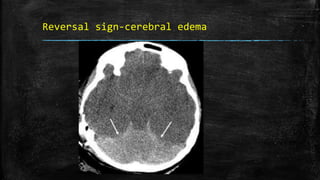

Reversal sign-cerebral edema

• #75 Reversal sign. Axial noncontrast CT scan of the brain in a child with severe head injury shows low attenuation of the cerebral hemispheres with complete loss of gray matter–white matter differentiation, small temporal horns, and effacement of the basal cisterns. The findings are suggestive of cerebral edema. There is relative preservation of the cerebellum (arrows) with hyperattenuation (‘white cerebellum’)